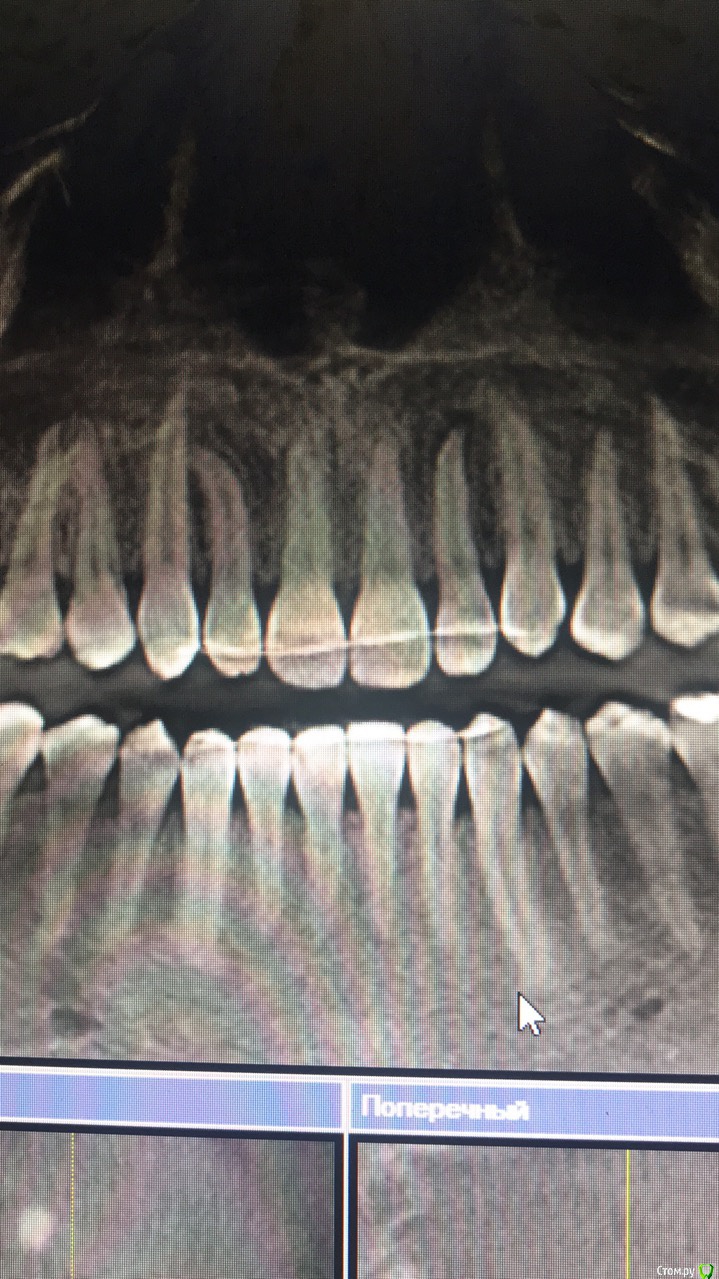

figboass Опубликовано 30 марта, 2018 Поделиться Опубликовано 30 марта, 2018 (изменено) Зуб 2.2, не лечен, никак не беспокоит , на Rg периодонтит. Месяц назад ушиб 1.1 был . Из -за этого? Что делать ? Изменено 30 марта, 2018 пользователем figboass Ссылка на комментарий

St. Опубликовано 30 марта, 2018 Поделиться Опубликовано 30 марта, 2018 На всякий случай проверить температурными пробами действительно ли нерв умер. 99% что да.А так стандартное лечение канала.Что касается причины вариантов несколько - травма, трещина, ортодонтия Ссылка на комментарий

Паращук Роман Опубликовано 30 марта, 2018 Поделиться Опубликовано 30 марта, 2018 Зуб 2.2, не лечен, никак не беспокоит , на Rg периодонтит. Месяц назад ушиб 1.1 был . Из -за этого? Что делать ?проверить термопробами на предмет живой ли,далее по ситуации. Ссылка на комментарий

figboass Опубликовано 1 апреля, 2018 Автор Поделиться Опубликовано 1 апреля, 2018 живой , реагируетчто далее?)) Ссылка на комментарий

dentikl Опубликовано 2 апреля, 2018 Поделиться Опубликовано 2 апреля, 2018 живой , реагируетчто далее?))сделать кт Ссылка на комментарий